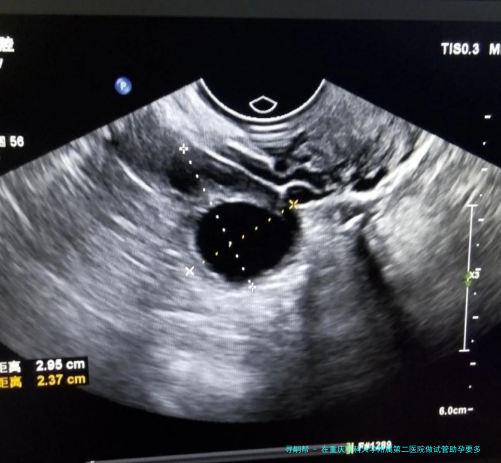

在重庆医科大学附属第二医院做试管助孕要多少费用?包括哪几个方面的花费?